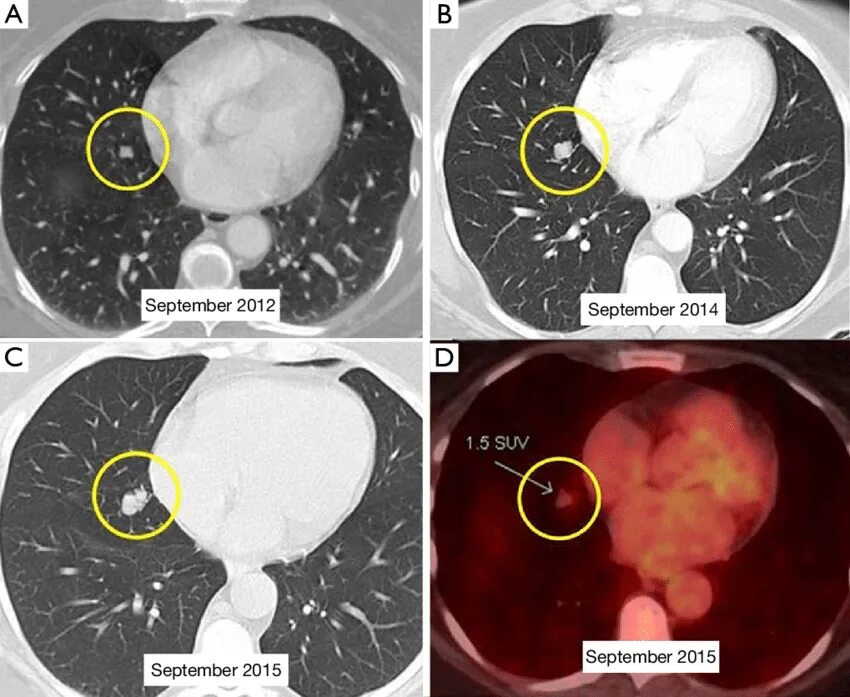

Ct search